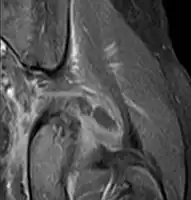

| Transverse T2 magnetic resonance imaging section through the hip region showing abscess collection in a patient with pyomyositis. | |